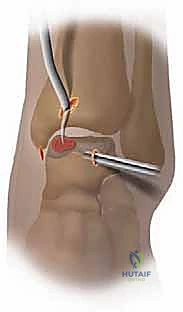

4. Microfracture Technique

This is the core of our procedure, designed to stimulate fibrocartilage formation. We use dedicated small-joint microfracture awls.

* Awl Selection: Choose an awl with an appropriate angle and tip to access the lesion effectively. We want a sharp, precise instrument to create clean perforations. The advantage of awls over drills or burrs is the avoidance of thermal necrosis.

* Penetration:

* Hold the awl perpendicular to the lesion surface. This is critical to ensure the holes are straight and allow maximal marrow access.

* Gently tap or push the awl into the subchondral bone.

* The depth of penetration should be 2 to 4 mm, just deep enough to penetrate the subchondral bone plate and reach the vascularized marrow space. Going too deep risks creating subchondral cysts or weakening the bone.

* Surgical Warning:

> Surgical Warning: Avoid creating excessively deep holes, which can weaken the subchondral bone and potentially lead to cyst formation. Conversely, too shallow holes will not reach the vascularized marrow.

* Spacing: Create a series of holes, typically 3 to 4 mm apart, across the entire débrided OLT surface. The goal is to create a "champagne effect," where blood and marrow elements visibly egress from each hole. This indicates successful penetration into the vascularized bone marrow.